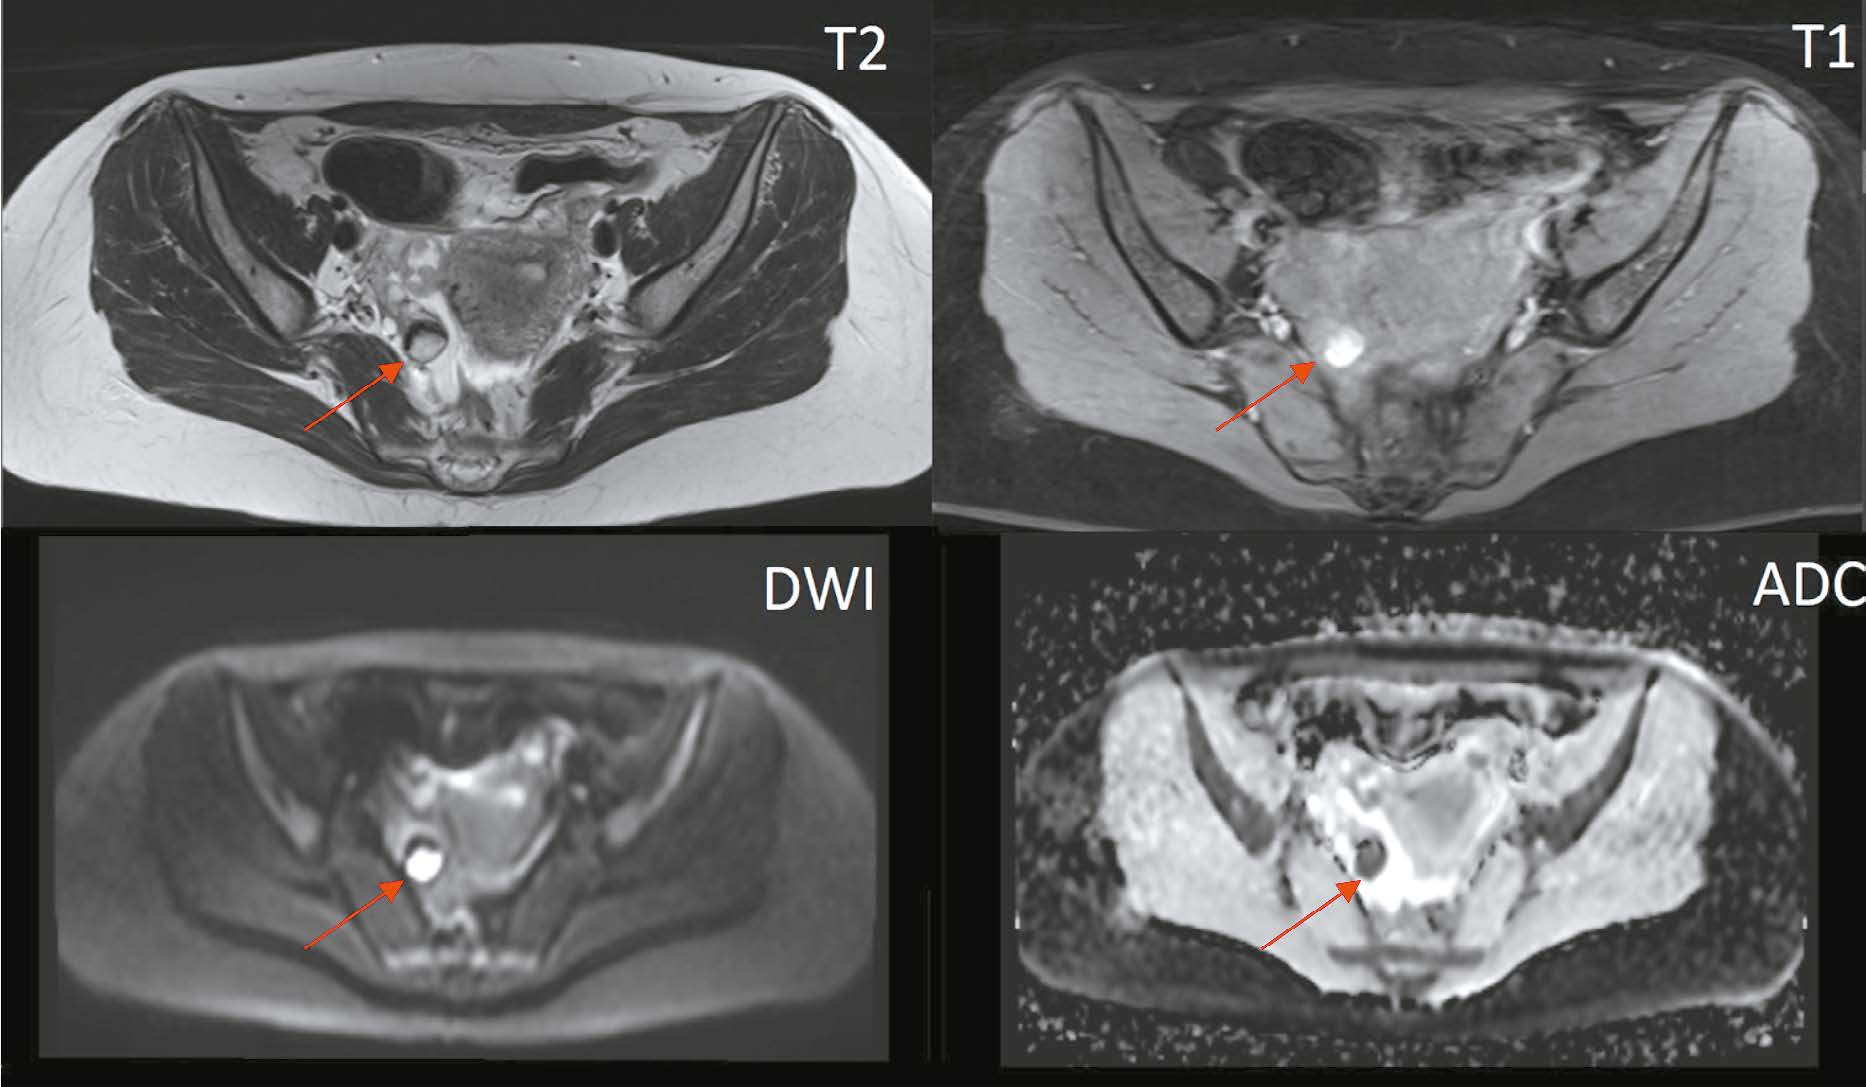

Magnetic resonance imaging in diagnosis of serous adenocarcinoma of fallopian tubes: a case report

Serous adenocarcinoma of fallopian tubes is an extremely rare and difficult to diagnose type of cancer of the female reproductive system. This condition is often asymptomatic or has a non specific clinical presentation including serosanguineous vaginal discharge and colic like pain in the lower abdomen and pelvis. These symptoms are reported in the literature as the Latzko’s triad and are considered pathognomonic for tubal cancer, but their combination is observed in less than 15% of patients. The low incidence and lack of the pathognomonic clinical presentation lead to many diagnostic errors or detection of advanced disease, which significantly worsens the patient’s prognosis. An accurate surgical diagnosis is made in only 4% of cases. This case report describes serous adenocarcinoma of fallopian tubes with all signs of the Latzko’s triad and MRI suggestive of serous adenocarcinoma of fallopian tubes at a preoperative stage.

882-892